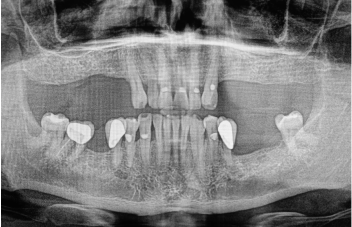

Leczenie bezzębia - bezzębie

Leczenie bezzębia jest dostosowywane do indywidualnych potrzeb pacjenta. Nowoczesne techniki minimalizują dyskomfort, skracają czas leczenia i zapewniają pacjentom estetyczny, trwały efekt oraz pełną funkcję żucia.